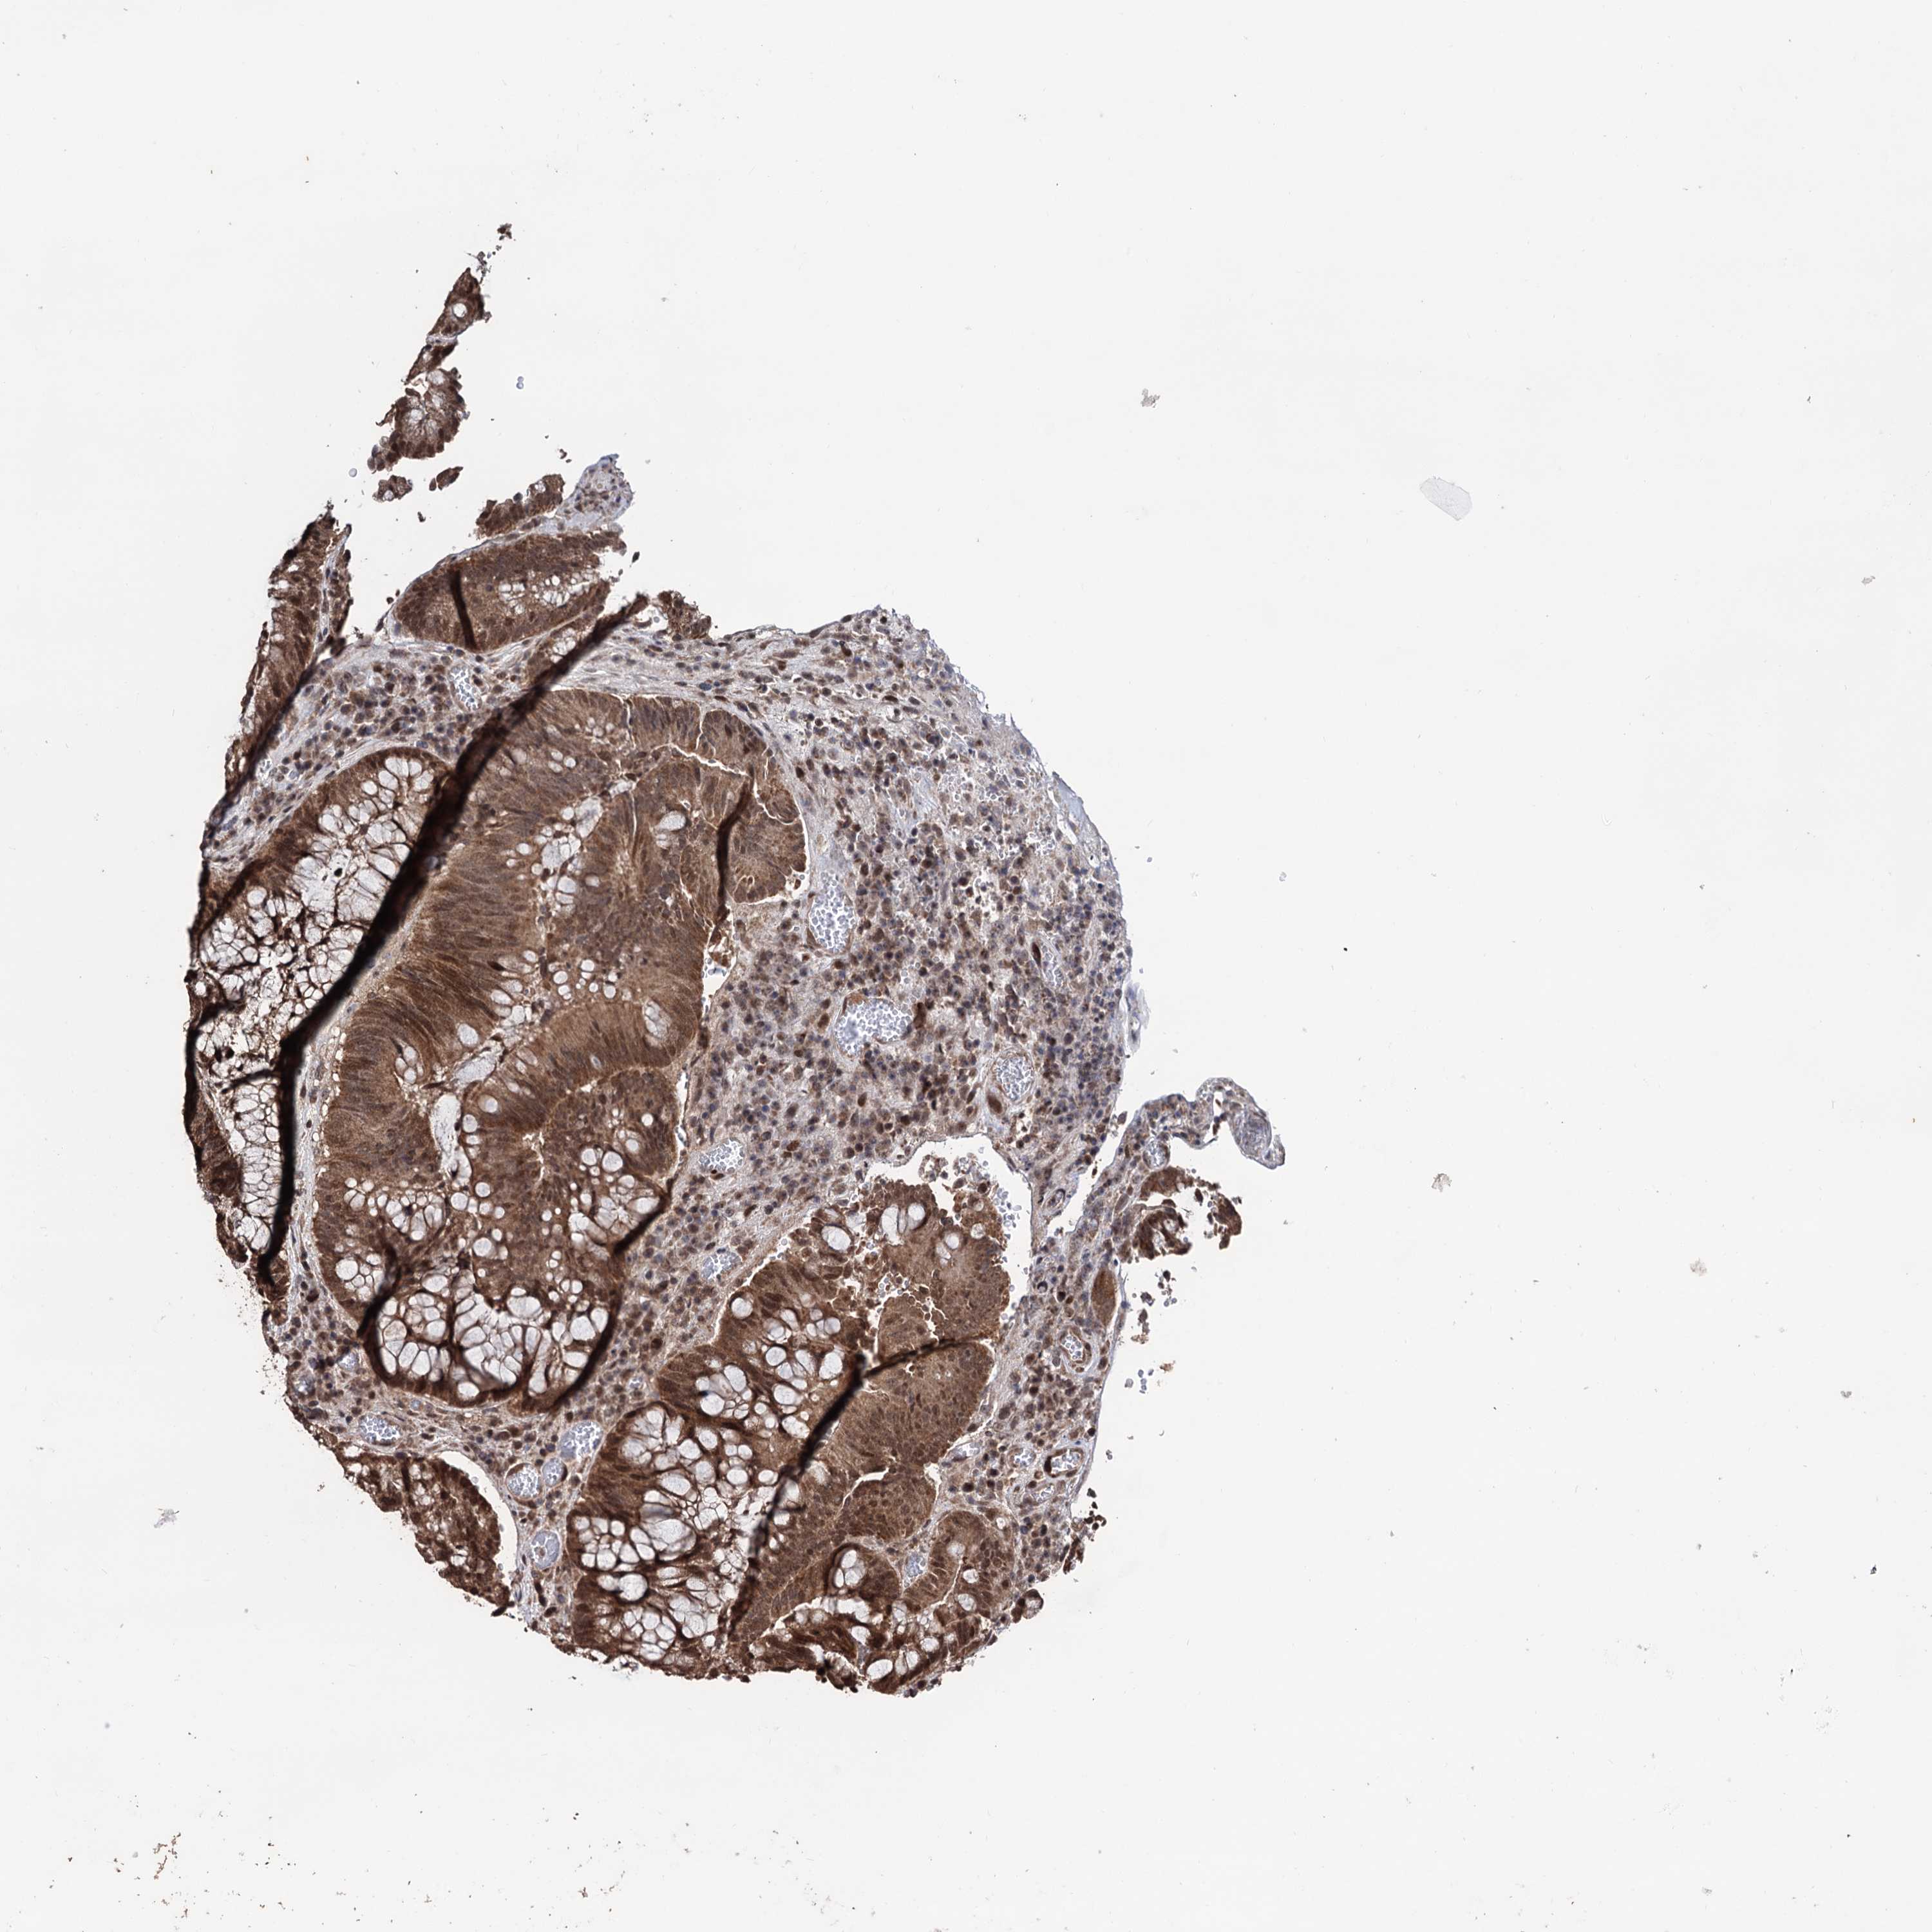

CANCER COLORECTAL CANCER Show tissue menu

Colorectal cancer

Human cancer

Rectum adenocarcinoma